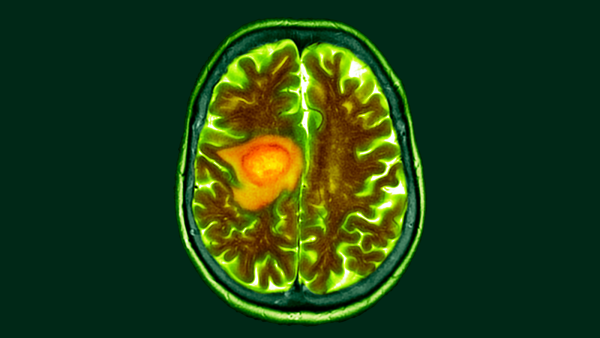

Під час розробки мРНК-вакцин для пацієнтів з пухлинами головного мозку у 2016 році наша команда під керівництвом дитячого онколога Еліаса Сайюра виявила, що мРНК може навчати імунну систему знищувати пухлини, навіть якщо мРНК не пов'язана з раком.

Зміна дієти може полегшити лікування раку мозку, згідно з попередніми дослідженнями